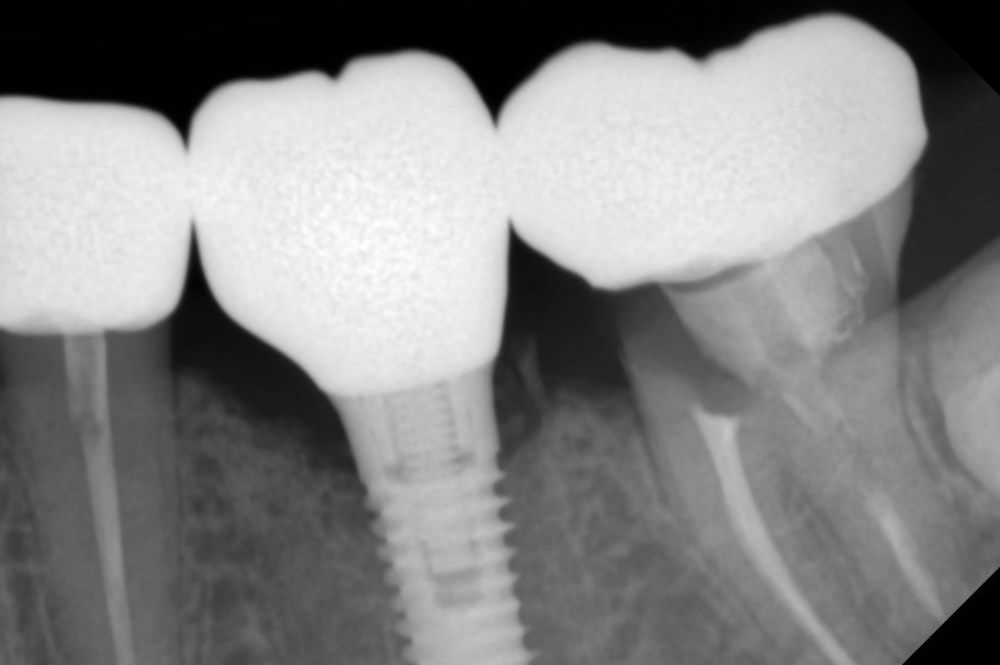

Имплантация жевательных зубов,

это самая востребованная операция.

рентген имплантатоы

фото коронок